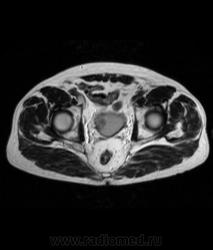

Для динамического контрастирования требуется инъектор, у нас с ним технические неполадки, поэтому контрастное вещество вводим от руки. Но в данном случае четко видно проростание опухолевого компонента через мышечный слой мочевого пузыря, даже некоторой инфильтрацией паравезикальной клетчатки. По гистологии плоско-клеточный рак. У пациента множественные метастазы в легких.